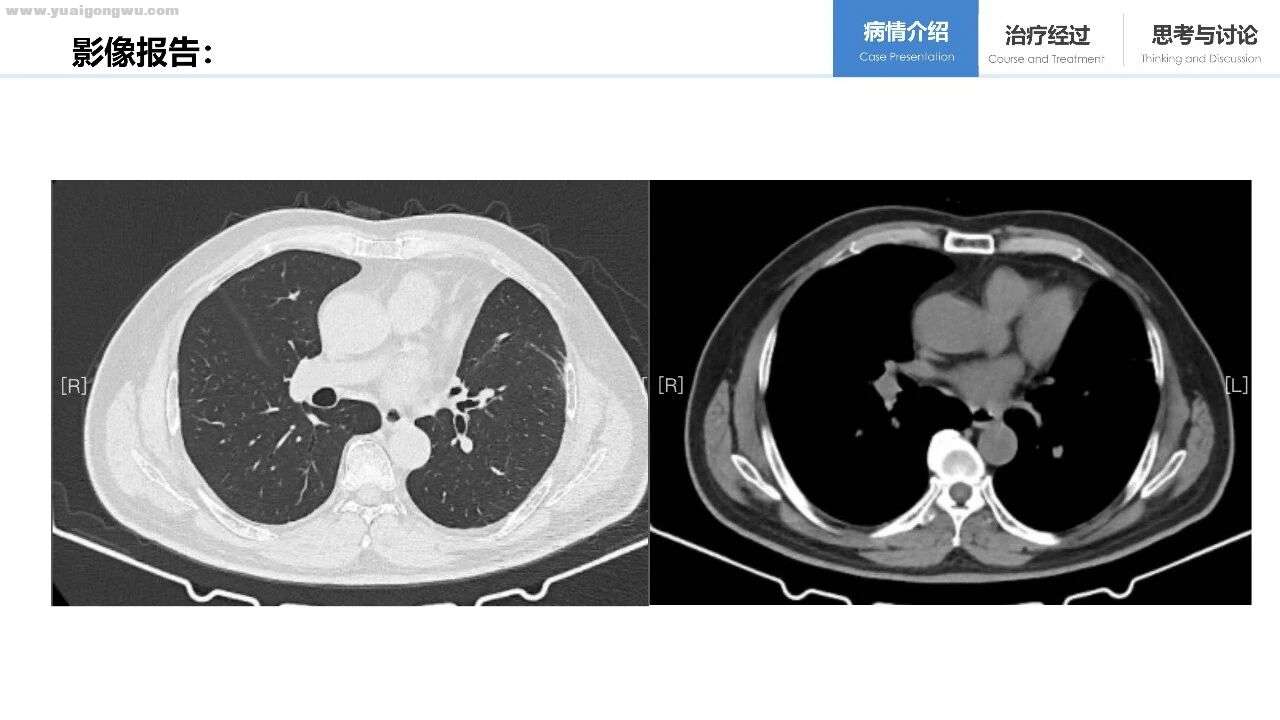

贺伟教授 患者临床影像表现典型,诊断较为明确。左下肺结节具有典型恶性征象,肺门、纵膈及全身多发淋巴结均存在转移。肺周围可见磨玻璃密度影伴局部网格影,不排除癌性淋巴结转移可能。影像报告显示双肺散在结节,考虑存在双肺转移。脑部核磁提示脑实质多发转移灶,但根据现有脑部影像资料,未见明确脑膜转移征象。若从影像层面确认脑膜转移,需核磁报告提供全面多序列影像以辅助判断。